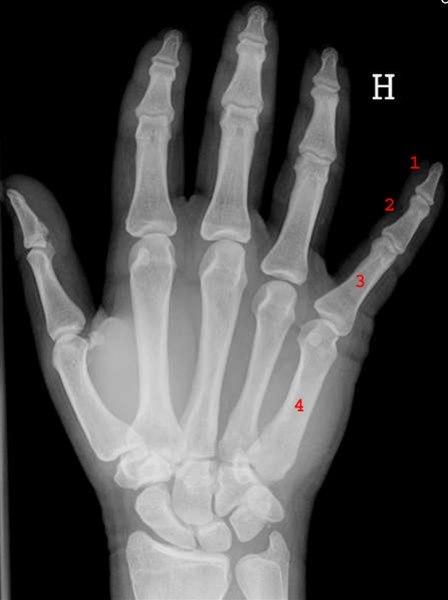

- Beinbrudd

- En lang rekke ulike beinbrudd kan oppstå i hånden

- Feilstilling etter skade

- Lokalisert ømhet på bruddsted

- Røntgen kan unntaksvis være til nytte